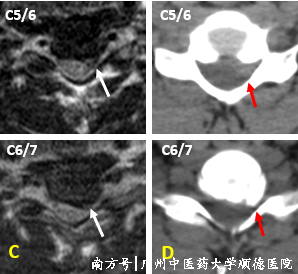

↑ A 颈椎曲度反弓,B C5/6、C6/7椎间盘突出,神经受压。

↑ MRI提示C5/6、C6/7椎间盘突出,左侧神经受压,C6/7突出伴钙化。